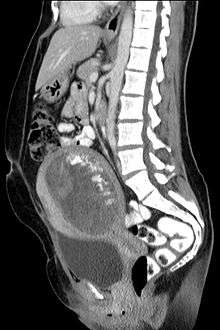

The diagnosis is strongly suggested by ultrasound (sonogram), but definitive diagnosis requires histopathological examination. On ultrasound, the mole resembles a bunch of grapes ("cluster of grapes" or "honeycombed uterus" or "snow-storm"[14]). There is increased trophoblast proliferation and enlarging of the chorionic villi.[15] Angiogenesis in the trophoblasts is impaired as well.[15]